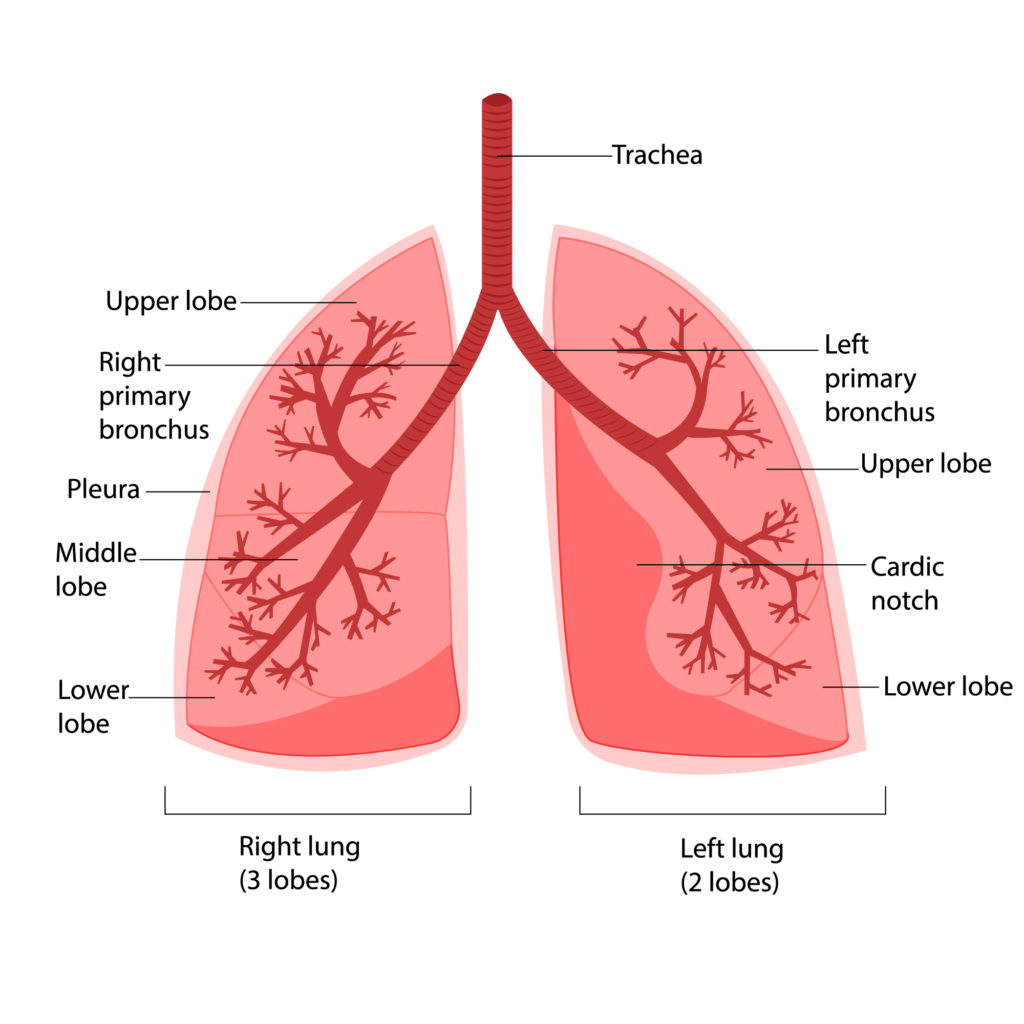

Η Ανατομία του πνεύμονα

Κάθε πνεύμονας υποδιαιρείται σε μικρότερα τμήματα που ονομάζονται λοβοί. Ο δεξιός πνεύμονας αποτελείται από τρεις λοβούς: τον άνω, μέσο και κάτω λοβό, ενώ ο, λίγο μικρότερος, αριστερός πνεύμονας αποτελείται από δύο λοβούς: τον άνω και κάτω. Συνολικά οι πνεύμονές μας ζυγίζουν 900 έως 1000 γραμμάρια. Ο πνεύμονάς μας γεμίζει με ατμοσφαιρικό αέρα ο οποίος μπαίνει από το στόμα και τη μύτη, περνάει από τον φάρυγγα, τον λάρυγγα και την τραχεία ώστε να καταλήξει στους πνεύμονες. Στη συνέχεια, η τραχεία διακλαδίζεται υπό την μορφή κλαδιών δένδρου σε πολύ μικρούς αεραγωγούς, δηλαδή μικρούς σωλήνες, και καταλήγει σε μικρούς σάκους, τις κυψελίδες, στις οποίες γίνεται η ανταλλαγή των αερίων. Έτσι ο πνεύμονας με τους αεραγωγούς του θυμίζει ένα δένδρο.